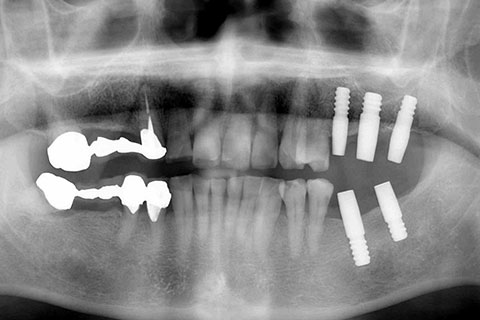

症例2

治療前

インプラント埋入時

治療後

- 年齢・性別

- 57歳男性

- 治療期間

- 3ヶ月

- 抜歯

- なし

- 治療費

- 154万円

- 備考

- 左上5.6.7 及び左下6.7欠損

- 治療内容

- 左上5.6.7と左下6.7欠損部にインプラント埋入

- 施術の副作用(リスク)

- オペによる知覚障害。インプラントによる歯肉炎。インプラント脱落。